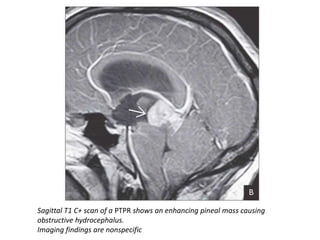

Sagittal T1 C+ scan of a PTPR shows an enhancing pineal mass causing

obstructive hydrocephalus.

Imaging findings are nonspecific

Sagittal T1 C+scan of a PTPR shows an enhancing pineal mass causing obstructive hydrocephalus. Imaging findings are nonspecific